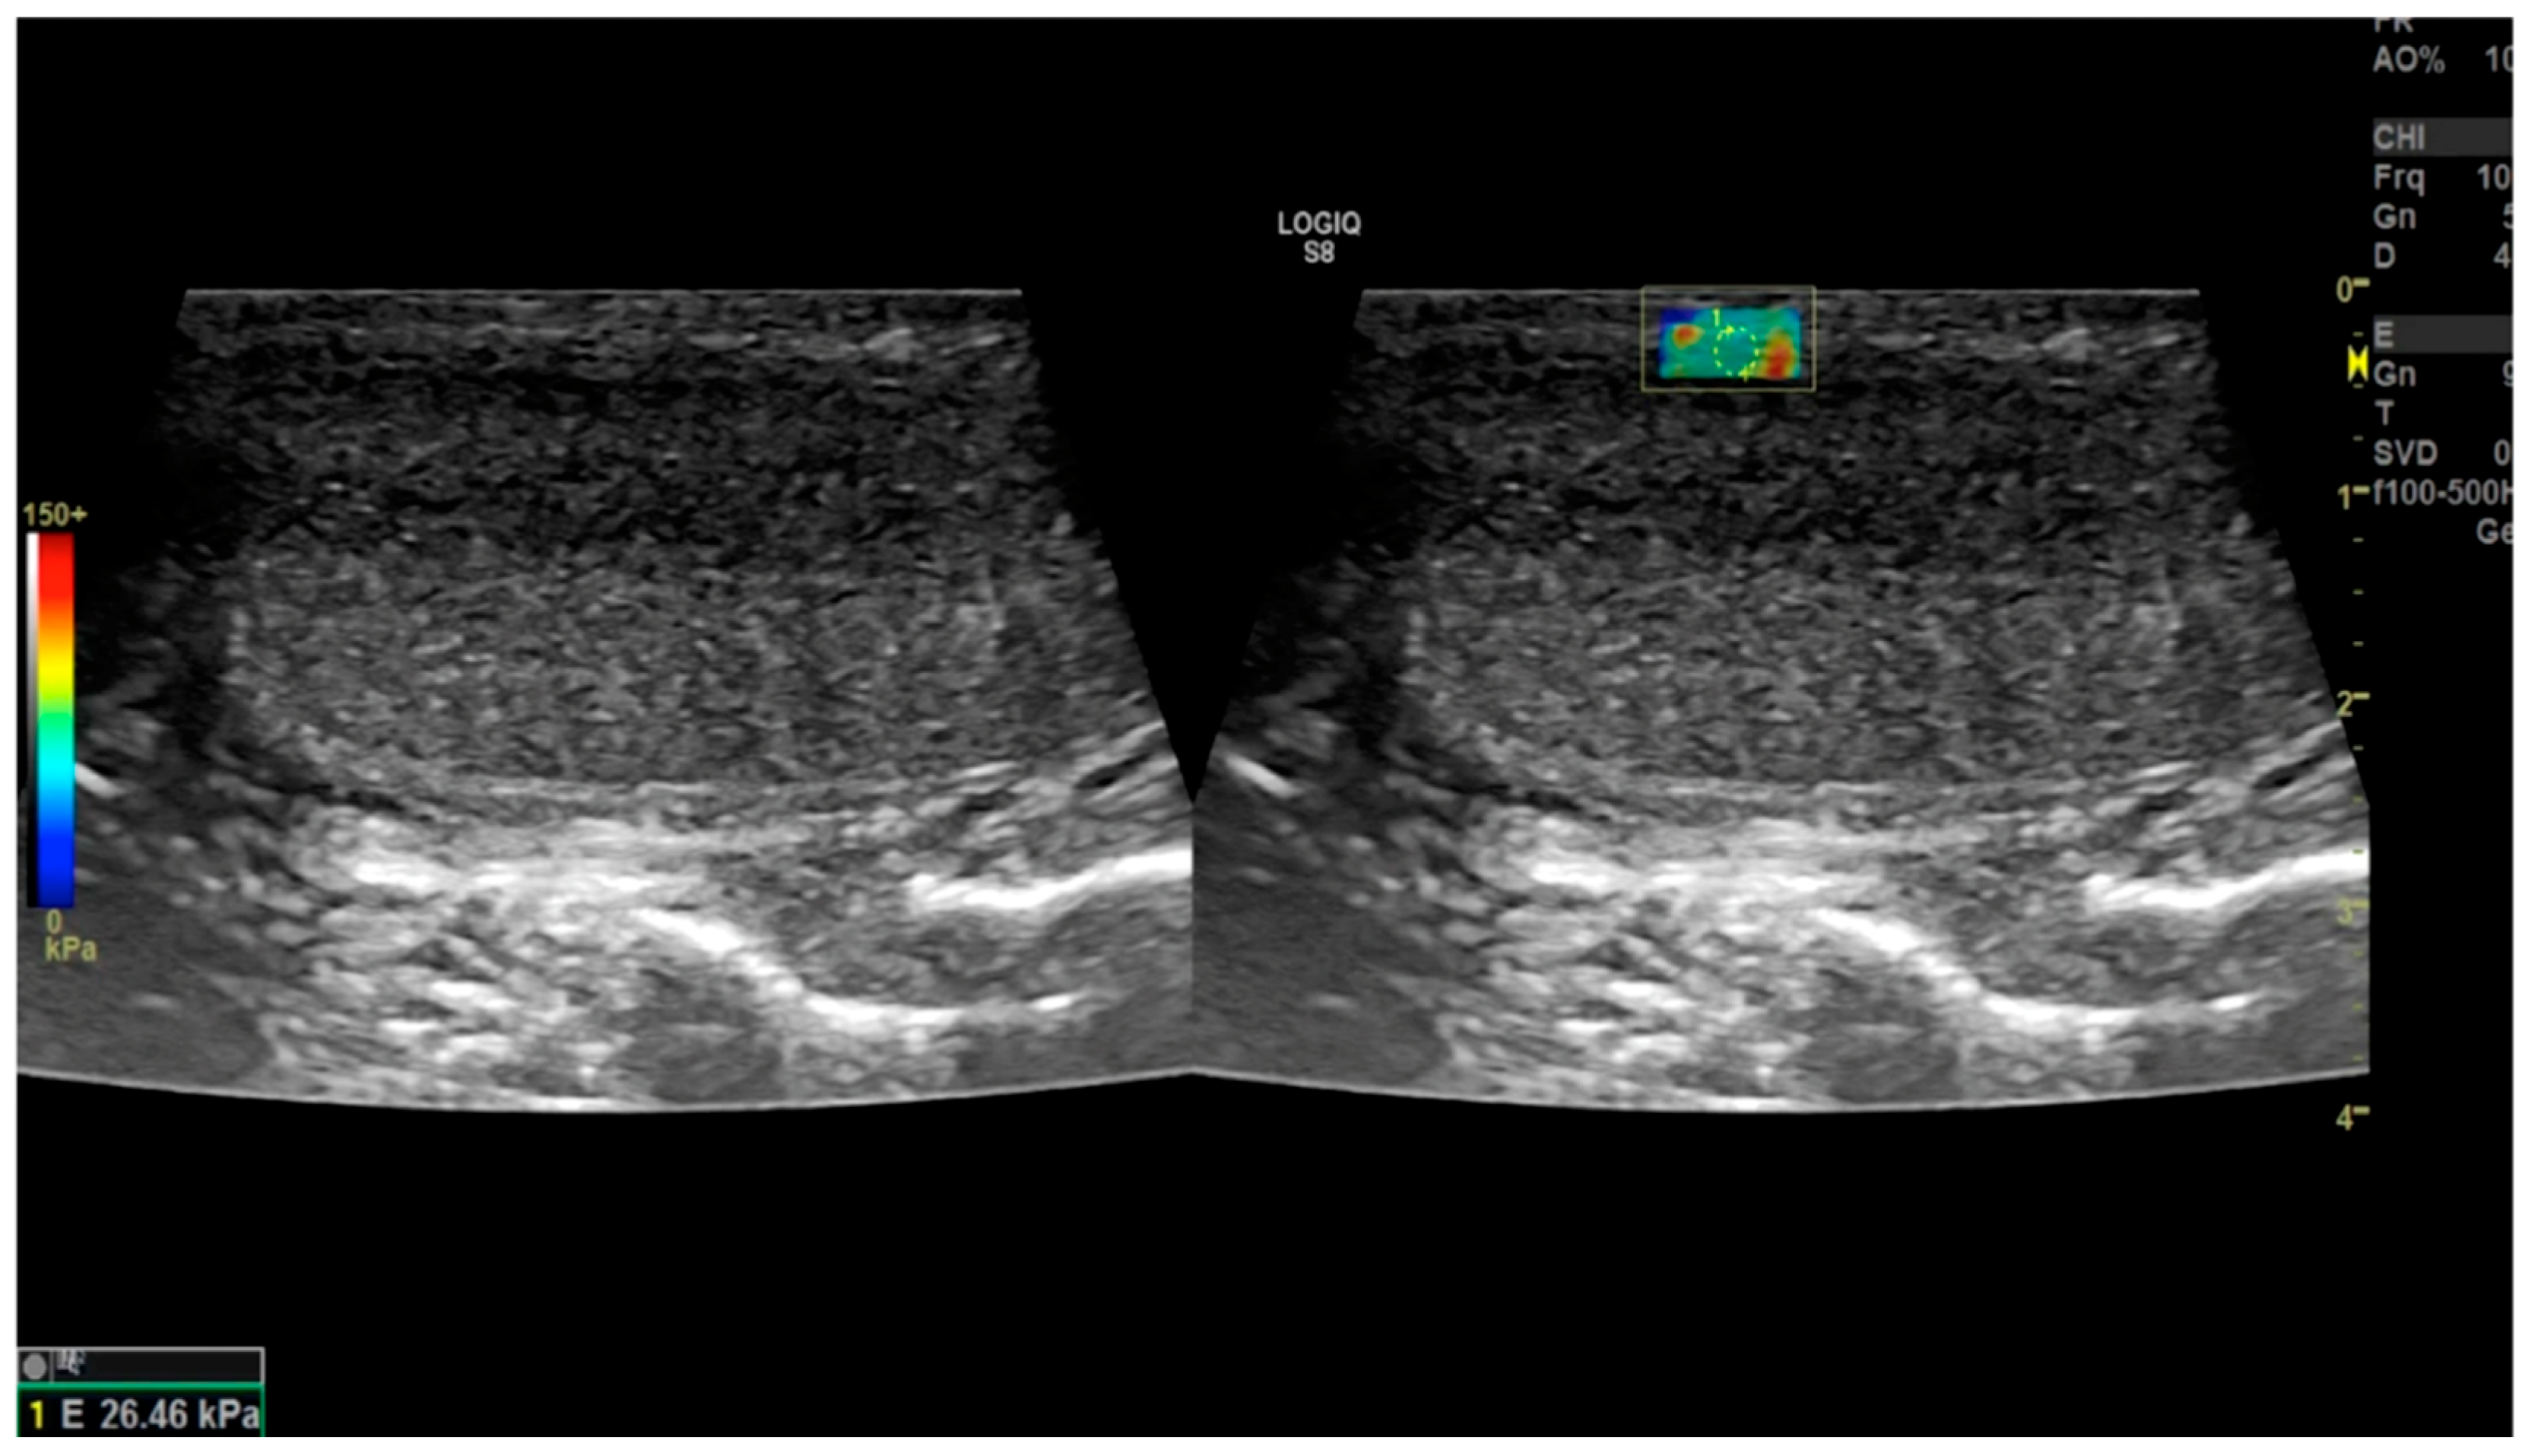

2.3.2. Shear-Wave Elastography

2.4.7. Trama et al. (2022) [44]

2.4.8. Zhao et al. (2024) [45]